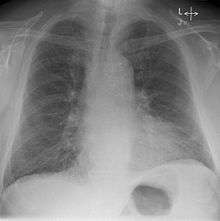

Kerley lines

Kerley lines are a sign seen on chest radiographs with interstitial pulmonary edema. They are thin linear pulmonary opacities caused by fluid or cellular infiltration into the interstitium of the lungs. They are named after Peter Kerley.[1]